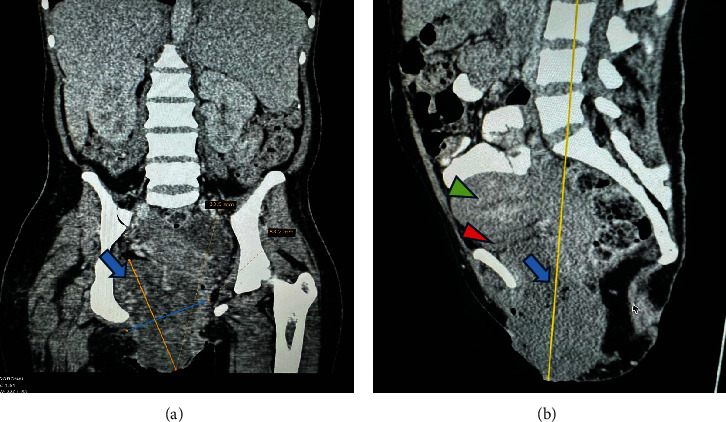

Background: Metastatic vulvar choriocarcinoma, a rare ectopic gestational trophoblastic neoplasia (GTN), often presents a diagnostic challenge due to its mimicry of other conditions, particularly in resource-limited settings. Its primary symptom is abnormal vaginal bleeding without a clear cause. Consequently, diagnosing and managing it poses difficulties for many low-resource health facilities, as evidenced by the current case. Case Presentation: We present the case of a 25-year-old, P2+2+2L2, who had a large painless, bleeding vulva mass for nearly 5 months. This followed a spontaneous abortion the month prior. The mass gradually increased in size and was accompanied by fever, pus discharge, and weight loss. Despite being treated at multiple health facilities for a vulvar abscess, there was no improvement. A diagnosis was finally made at a tertiary facility where elevated quantitative serum beta-human chorionic gonadotropin (hCG) (β-hCG) was noted. Due to uncontrollable vulva bleeding, she was referred to another tertiary facility for emergency radiotherapy. Following stabilization, chemotherapy was administered using the EMA-CO protocol. Conclusion: The report highlights the difficulty in diagnosing vulvar choriocarcinoma, underscoring the importance of a high index of suspicion. Clinical tests such as serum (β-hCG) and imaging studies are crucial for diagnosis. In resource-limited settings, a simple strip-based urine pregnancy test with serial dilutions can be sufficient for diagnosing and managing vulvar choriocarcinoma.